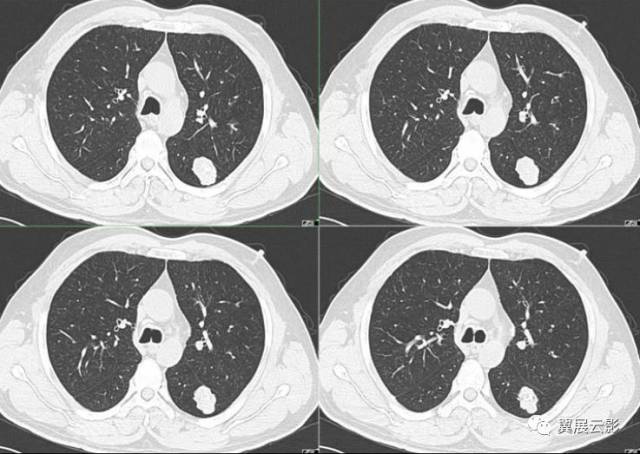

刘懿博士说肺癌二五九〇切之前知道俩肺结节是良性但不是一种病